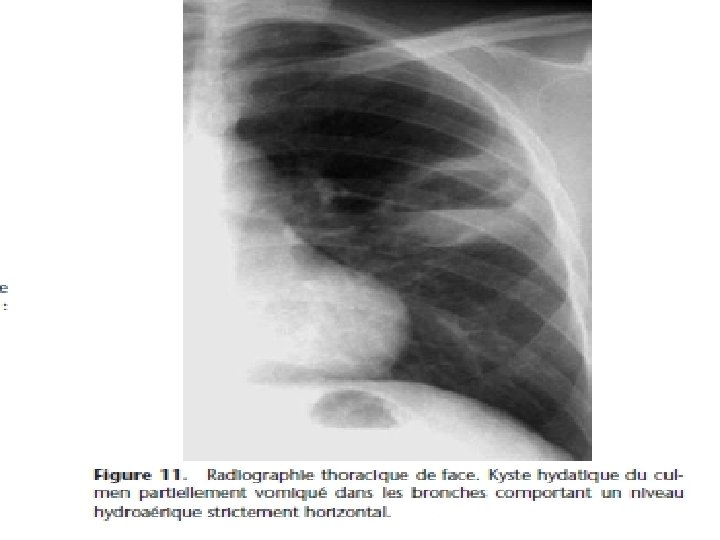

4) Pyopneumokyste : stade à la fois clinique et radiologique Clinique= signes fonctionnels et signes généraux Radiologique= images hydroaériques - Rarement à niveau rectiligne de l’abcès du poumon - Image de membrane ondulée plus fréquemment - Ainsi qu’image en nénuphar ou en coucher de soleil - Exceptionnellement image en double arc d’Ivassinévitch

5) Kyste vomiqué: exclusivement radiologique (3 cas) - Image en grelot: opacité ronde au sein d’une cavité ronde - Image en cocarde: opacité ronde entourée d’une clarté en anneau - Image de membrane pelotonnée ou d’incarcération de membranes Lorsque le kyste est évacué en totalité, liquide et membrane, on peut avoir un aspect de guérison, avec ou sans cavité résiduelle; éventualité exceptionnelle.

Imagerie médicale